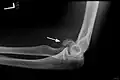

-

Mit ESIN versorgter schultergelenknaher Oberarmbruch beim Kind. Ausheilungsbild mit deutlich sichtbarem Frakturkallus (Pfeil) -